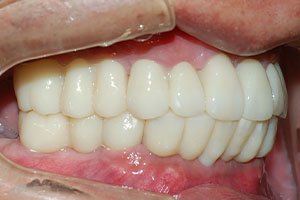

치료증례 전후사진

Before & After